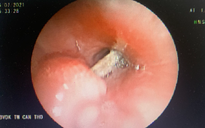

Thức ăn nghẹt dính vào ống nội khí quản sau khi hồi sức tim phổi thất bại

BS Tuệ cho biết sau khi xảy ra sự cố, bé được đưa qua hai trạm y tế trước khi gọi cấp cứu 115. Khi lực lượng cấp cứu tiếp cận, bé đã trong tình trạng ngừng tim, ngừng thở, đồng tử giãn, không còn phản xạ. Dù được hồi sức tim phổi tích cực trong hơn 70 phút, bé vẫn không qua khỏi, để lại nỗi mất mát sâu sắc cho gia đình và cộng đồng.